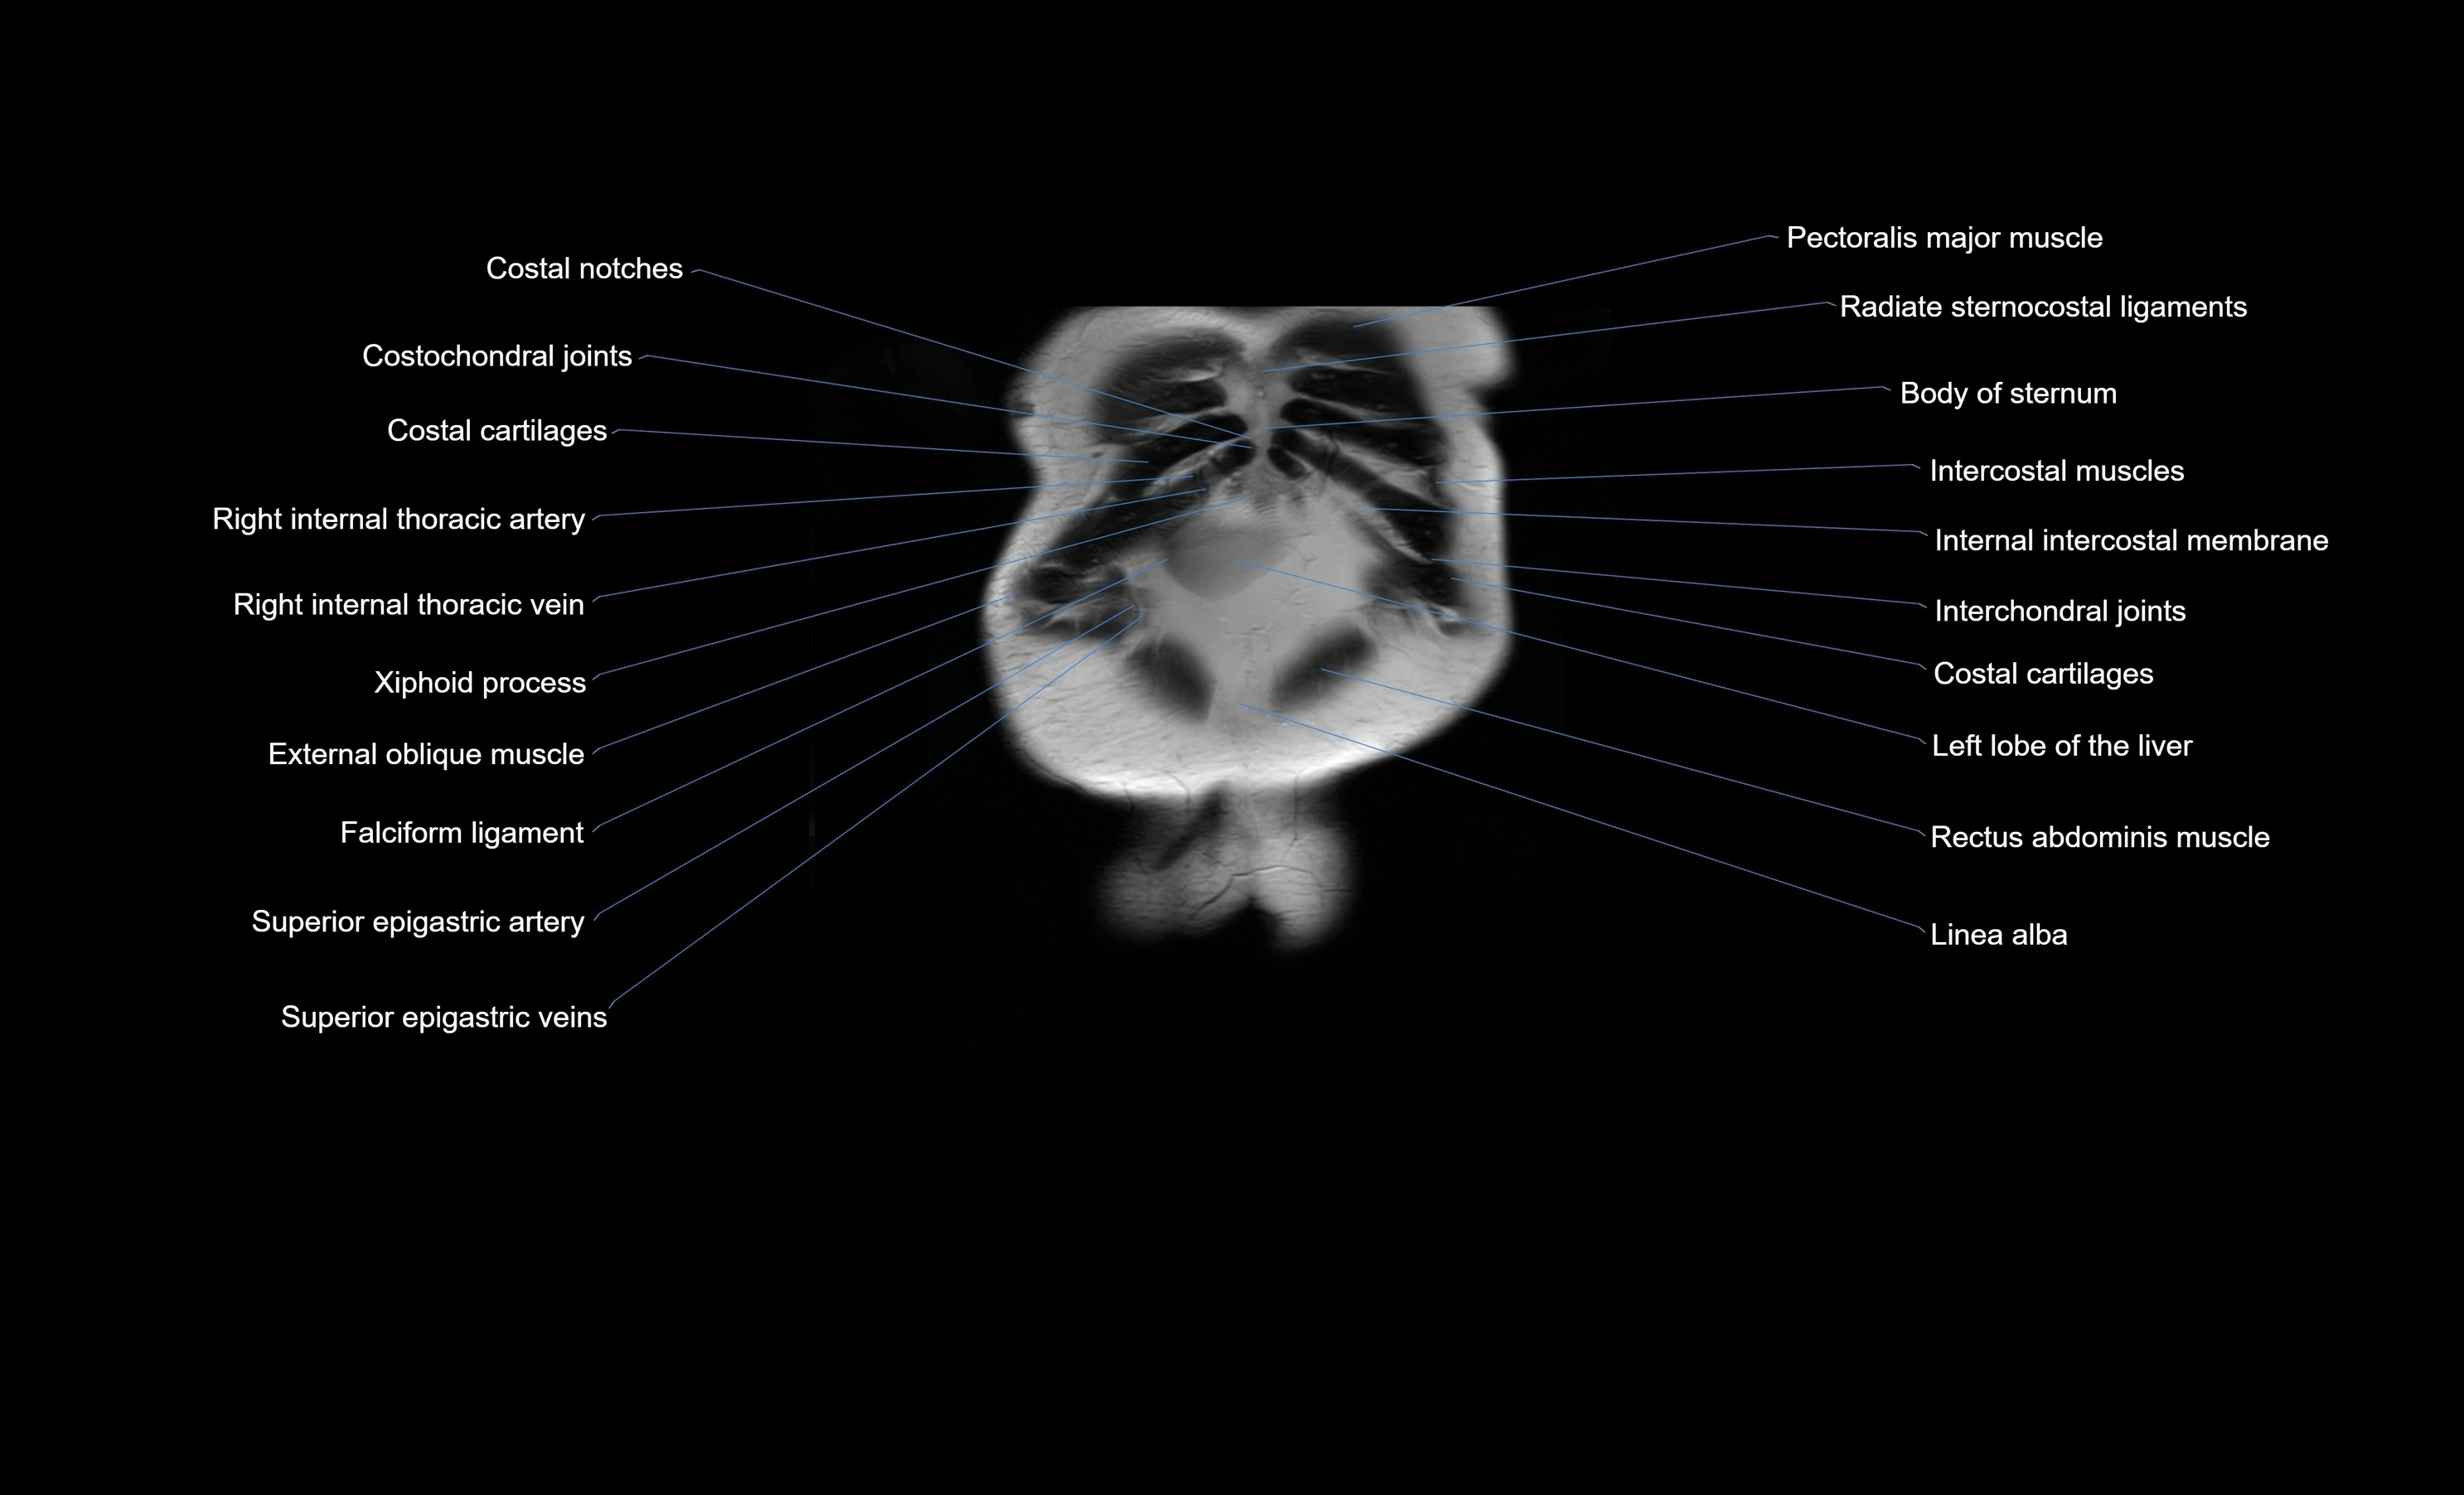

- Costochondral joints

- Intercostal muscles

- Internal thoracic artery

- Internal thoracic veins

- Left lobe of liver

- Linea alba

- Rectus abdominis muscle

- Superior epigastric artery

- Superior epigastric veins

- Falciform ligament (liver)